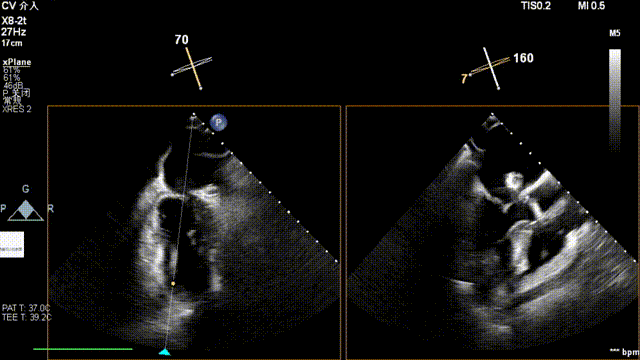

术中超声(关键步骤)

最终在A3P2位置夹合,前叶夹合量10mm,后叶夹合量8mm,剩余瓣口面积3.45cm²,平均跨瓣压差2mmHg,反流基本消除。